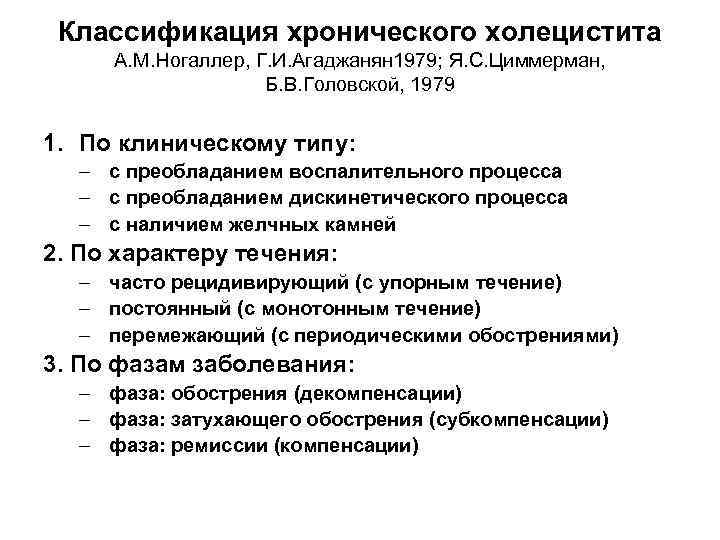

Классификация хронического холецистита А. М. Ногаллер, Г. И. Агаджанян 1979; Я. С. Циммерман, Б. В. Головской, 1979 1. По клиническому типу: – с преобладанием воспалительного процесса – с преобладанием дискинетического процесса – с наличием желчных камней 2. По характеру течения: – часто рецидивирующий (с упорным течение) – постоянный (с монотонным течение) – перемежающий (с периодическими обострениями) 3. По фазам заболевания: – фаза: обострения (декомпенсации) – фаза: затухающего обострения (субкомпенсации) – фаза: ремиссии (компенсации)

Классификация хронического холецистита А. М. Ногаллер, Г. И. Агаджанян 1979; Я. С. Циммерман, Б. В. Головской, 1979 1. По клиническому типу: – с преобладанием воспалительного процесса – с преобладанием дискинетического процесса – с наличием желчных камней 2. По характеру течения: – часто рецидивирующий (с упорным течение) – постоянный (с монотонным течение) – перемежающий (с периодическими обострениями) 3. По фазам заболевания: – фаза: обострения (декомпенсации) – фаза: затухающего обострения (субкомпенсации) – фаза: ремиссии (компенсации)

Классификация хронического холецистита А. М. Ногаллер, Г. И. Агаджанян 1979; Я. С. Циммерман, Б. В. Головской, 1979 4. По характеру дискинезий – нарушения сократительной функции желчного пузыря: • гиперкинез желчного пузыря • гипокинез желчного пузыря (без изменения тонуса – нормотония, с понижением тонуса – гипотония) – с нарушением тонуса сфинктерного аппарата желчвыводящих путей: • гипертонус сфинктера Одди, гипертонус сфинктера Люткенса, • гипертонус обоих сфинктеров 5. По степени тяжести: – легкое течение – средстей степени тяжести – тяжелое 6. Основные клинические синдромы: болевой, диспептический, кардиалгический, предменструального напряжения, солярный, вегетативной дисфункции, аллергический

Классификация хронического холецистита А. М. Ногаллер, Г. И. Агаджанян 1979; Я. С. Циммерман, Б. В. Головской, 1979 4. По характеру дискинезий – нарушения сократительной функции желчного пузыря: • гиперкинез желчного пузыря • гипокинез желчного пузыря (без изменения тонуса – нормотония, с понижением тонуса – гипотония) – с нарушением тонуса сфинктерного аппарата желчвыводящих путей: • гипертонус сфинктера Одди, гипертонус сфинктера Люткенса, • гипертонус обоих сфинктеров 5. По степени тяжести: – легкое течение – средстей степени тяжести – тяжелое 6. Основные клинические синдромы: болевой, диспептический, кардиалгический, предменструального напряжения, солярный, вегетативной дисфункции, аллергический